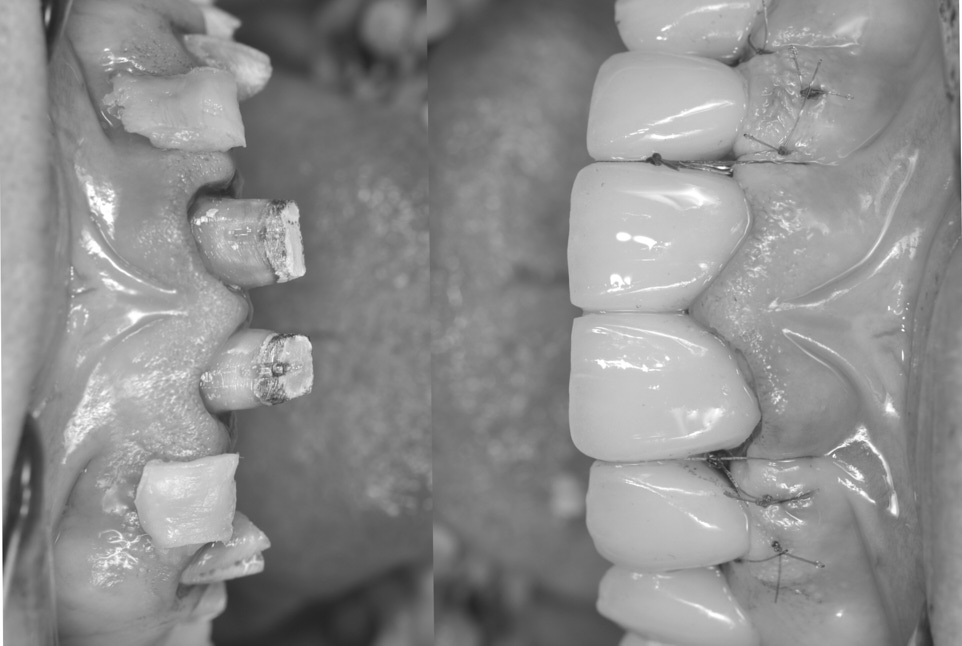

Фото 3.

Якщо розглядати з оклюзійного боку, можна легко помітити, що ясна у зоні двох бічних різців увігнуто. Це слід виправити за допомогою пластичної операції.

Фото 12.

Після фіксації керамічної реставрації, було накладено підвісні шви, щоб вони підтягували сполучнотканинний трансплантат та поверхневу оболонку в напрямку коронки.

Фото 15.

Вигляд збоку, з ідеальним ясенним профілем. Процес загоєння проходив відповідно до форми країв керамічної реставрації.

Фото 16.

Вигляд з іншого боку, з ідеальним ясенним профілем і таким самим зубоясенним переходом.